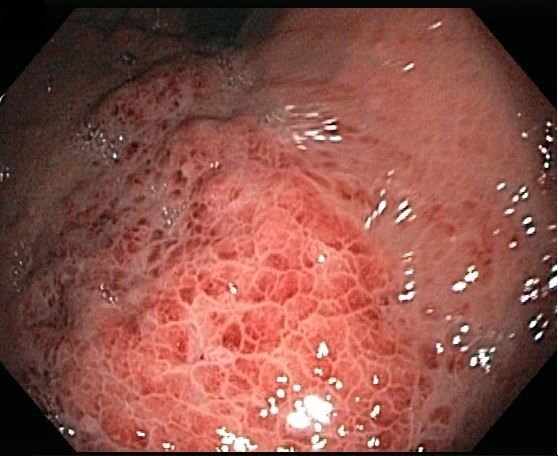

The EGD showed a Schatzki ring that was successfully dilated using an 18- to 20-mm balloon dilator. Noted in the cardia was a severely erythematous and mildly elevated gastric lesion (Figure 1). An EGD examination performed 2 years earlier showed similar findings but with mild erythema and nodular mucosa (Figure 2). Previous biopsies from that lesion had revealed mild chronic gastritis.

Results of a repeated biopsy of the lesion found oxyntic-type gastric mucosa with few dilated glands and background mild chronic inactive gastritis.